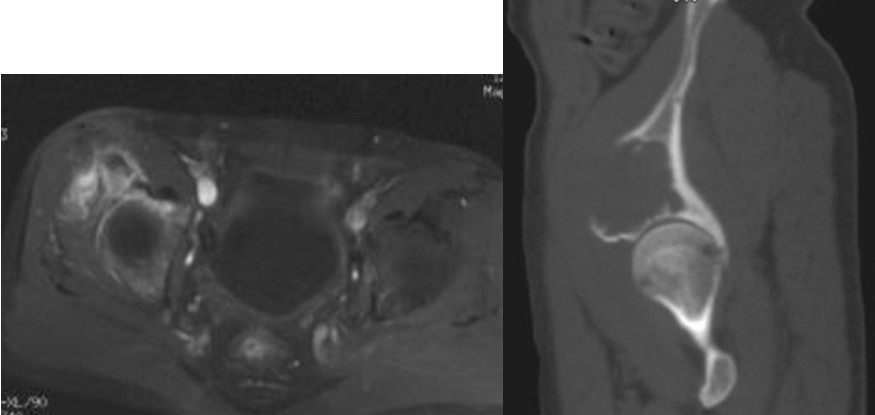

本组病例中不同部位髋臼转移癌的手术方式(图1):I型:髋臼下壁骨破坏、上壁及内、外侧壁完整, 采用肿瘤刮除、普通水泥型全髋置换术。II型:髋臼内、外侧壁破坏,上壁骨质完整, 采用带翼网杯+水泥型全髋置换术。 III型:髋臼上壁及内、外侧壁均破坏,采用肿瘤刮除后、骨水泥填充髋臼上壁骨缺损,带翼网杯+水泥型全髋或组合式人工半骨盆。IV型:孤立性骨盆转移, 以治愈为目的, 采用肿瘤整块切除,组合式人工半盆置换术。

Ⅲ型:髋臼内壁、顶部及外侧壁均破坏。仅使用带翼网杯的全髋假体是不够的。在这种情况下,需要在骨盆缺损处放置数根斯氏针以便于将位于解剖位置的髋臼假体所承受的应力传导至脊柱(1-3)。在大多数髋臼周围破坏广泛的病例,需要采用扩大的髂股骨切口入路,以便于探查骨盆内外侧区域。在显露清楚后,自髋臼缺损处沿残留的正常髂骨向骶髂关节方向钻入2-3根斯氏针,并越过关节达到骶骨。应采用较粗的斯氏针,术中还需要X线监测以保证斯氏针的位置。在钻入斯氏针的同时,应用手指触摸坐骨切迹,以保证斯氏针的方向,防止其穿入骨盆内壁。当髋臼缺损较大时,还可以自前部髂嵴向前柱的耻骨及后柱的坐骨钻入更多的斯氏针做进一步的加强。在髋臼假体顶部切断斯氏针,并安装带翼网杯,在髋臼深部可以用金属钛网加强骨水泥固定。术后病人可全部负重行走,但需置患肢外展中立位约4周时间以防止脱位。也有采用马鞍式假体置换的报道, Benevenia等对20例髋臼III型转移瘤患者进行了马鞍假体置换,术后MSTS 93评分平均16.6分,多数病人可以扶拐行走(5)。对于髋臼上壁及内、外侧壁均破坏的HarringtonIII型患者,本组病例中,有7例患者采用了肿瘤刮除后、于骶髂关节处植入3-4枚斯氏针, 骨水泥填充髋臼上壁骨缺损,水泥型全髋重建髋关节。其中,有2例患者出现下地后髋部痛疼,负重时髋部不稳定。考虑为负重时骶骨内斯氏针承受较大剪力, 出现髋关节不稳。因此,在本组病例中,我们对4例Ⅲ型患者实施了整块切除、可调式人工半骨盆置换术。术后6周患者可以扶拐下地行走。平均MSTS93评分为23.3分。

Ⅳ型:为了达到治愈而需要进行整块的髋臼切除。对于部分单一髋臼转移的病例,以及髋臼周围骨质破坏范围较大的病变,在广泛切除肿瘤后,重建髋关节(内半盆切除)有时较为困难。在这些病例,可以选择马鞍式假体。这种方法最开始用于全髋关节置换术后的骨缺损,后来也用于原发或转移性髋臼肿瘤的治疗。也可以选用带有固定翼,能固定于残存髂骨和耻骨支的定制型髋臼假体(7-9)。这种假体制作前通常需要进行CT模拟重建设计。固定方式常用螺丝钉和骨水泥。有时想要应用定制型假体达到理想的固定位置较为困难。对于骨盆环的完整性重建,纵向稳定是极其重要的,同时要考虑人工假体在术中的可操作性。定制型骨盆假体为非组配式,其髂骨固定螺钉是单轴向的,不能根据术中截骨情况调整假体,固定也不够牢固。 我们设计使用的可调式半骨盆假体,其髂骨固定钉改为双轴向或多轴向固定,假体与骨之间的界面为垂直压力、而非剪力,增加了稳定性,同时可以根据髂骨截骨的高度选择颈长的臼杯,利于安装和保持骨盆平衡(10)。组配式骨盆假体还考虑到骨盆纵向和侧方的稳定因素, 尽量达到恢复骨盆环连续性和稳定性的目的。对于髂骨区和髋臼上缘的骨缺损重建,钉棒系统简单,易于操作,但固定钉在骨内的应力较大,容易在负重的情况下对骨质产生切割,尤其骨质疏松的病人固定更加不稳,因此需用骨水泥加强。由于组配式人工骨盆是一个组合装置,因而体积较小,便于软组织覆盖,伤口感染率大大下降。

图1, 髋臼转移癌的分型示意图(北京大学人民医院)

图4,女,52岁,乳腺癌髋臼转移, Harrington III型

图5,男,69岁,肾癌髋臼转移, Harrington IV型